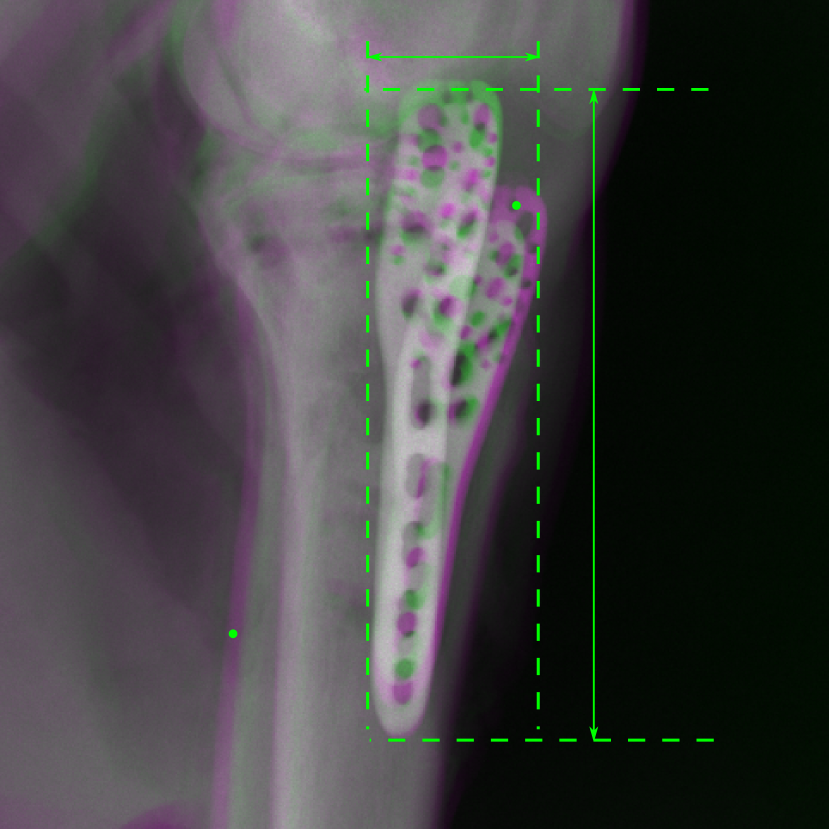

5.4 Real Knee Data with Metal Implants

Refer to caption

Figure 13: Three examples of synthetic perspective projection images for training, intensity window: [0, 4]. The appearance (e.g., image contrast and metal image resolution) of such DRR training images is different from that of real projection images in Fig. 14.

0superscript00^{\circ} perspective

(a) 32.56, 109.85

(b) 18.91, 19.54

(c) 28.11, 112.16

(d) 15.80, 19.27

0superscript00^{\circ} and 180superscript180180^{\circ} RGB

DRR reference

(e) 29.72, 111.80

(f) 17.14, 19.38

Pix2pixGAN

(g) 29.72, 111.80

(h) 17.50, 19.70

TransU-Net

(i) 29.72, 111.80

(j) 16.23, 19.25

Figure 14: The results for the real cadaver leg data. The green dots mark the positions of landmarks in the corresponding reference images. In the first column, the arrows indicate the bone cavity/fracture structures. In the second column, the solid lines mark the widths and heights of the metals. The green ones are measured from the DRR reference, while the red ones are measured in the corresponding perspective projection image. In the last column, the lines mark the centerlines of the metal screws, where the green lines are those from the reference image. The lengths of the lines in mm are displayed in their corresponding subcaptions. Intensity window: [0, 4]. Please zoom in for better visualization.

The complementary view setting for learning perspective deformation is also evaluated on real CBCT projection data. In this evaluation, real CBCT projection data from a dataset of knees with metal implants is used for testing, while DRRs created from volumetric CT datasets with inserted metals is used for training. Three exemplary DRR perspective projection images for training are displayed in Fig. 13, in which synthetic metal implants are inserted [34]. The appearance, e.g., image contrast and metal image resolution, of such DRR training images is different from that of real projection images in Fig. 14. In Fig. 14, the results for three knees, with and without metal implants, are displayed. The first and second rows are the 0superscript00^{\circ} and 180superscript180180^{\circ} perspective projections, respectively, rebinned to the virtual detector with geometric calibration based on their respective principal points and projections of the world origin. The third row displays their difference images, where the magnitude of deviation increases from the center towards the outside like it does in DRRs with an ideal scan trajectory (e.g., Fig. 6(e)), although real projection data suffer from various physical effects like beam hardening and Poisson noise. The fourth row displays the RGB stacks of 0superscript00^{\circ} and 180superscript180180^{\circ} perspective projection images. The magenta and green regions indicate structures with considerable perspective deformation, for example, the knee patella in Fig. 5.4, the top parts of the two metals in Fig. 5.4, and the bottom two screws in Fig. 5.4. The fifth row displays reference images, which are orthogonal projections of iterative reconstruction volumes from measured CBCT projection data. In the reference images, a total of five landmarks are selected, with the positions being marked by the green dots: In Fig. 5.4, two positions at the edges of the knee patella are marked; In Fig. 14(e) and Fig. 14(f), one position at the left edge of the fibula is marked for each image. In addition, a rectangular frame for the two metals is marked by the green dashed lines, while its width and height are indicated by the green solid lines, which are 29.71 mm and 111.99 mm, respectively. In Fig. 14(f), the centerlines of the bottom two screws are sketched by the green lines, which have the lengths of 17.14 mm (middle screw) and 19.38 mm (bottom screw). The corresponding rectangular frame for the two metals and the screw centerlines in the perspective projection images are marked as well, but in red color. In Fig. 14(a), the width and height of the metals are 32.56 mm and 109.85 mm, which have deviations of 2.84 mm and -1.95 mm to the reference ones, respectively. In Fig. 14(b), the centerline lengths are 18.91 mm and 19.54 mm, which have deviations of 1.77 mm and 0.16 mm, respectively. Although the bottom screw has little length deviation to the reference, the orientations of both screws are obviously deviated. The sixth row shows the results of Pix2pixGAN using 0superscript00^{\circ} and 180superscript180180^{\circ} polar inputs. For all of the landmarks, the green reference dots are all located accurately in the Pix2pixGAN images. The rectangular reference frame also accurately covers the metals in Fig. 14(g). In Fig. 14(h), although the two red centerlines do not exactly overlap with the green one, they are very close in lengths and orientations. Please zoom in for better visualization.